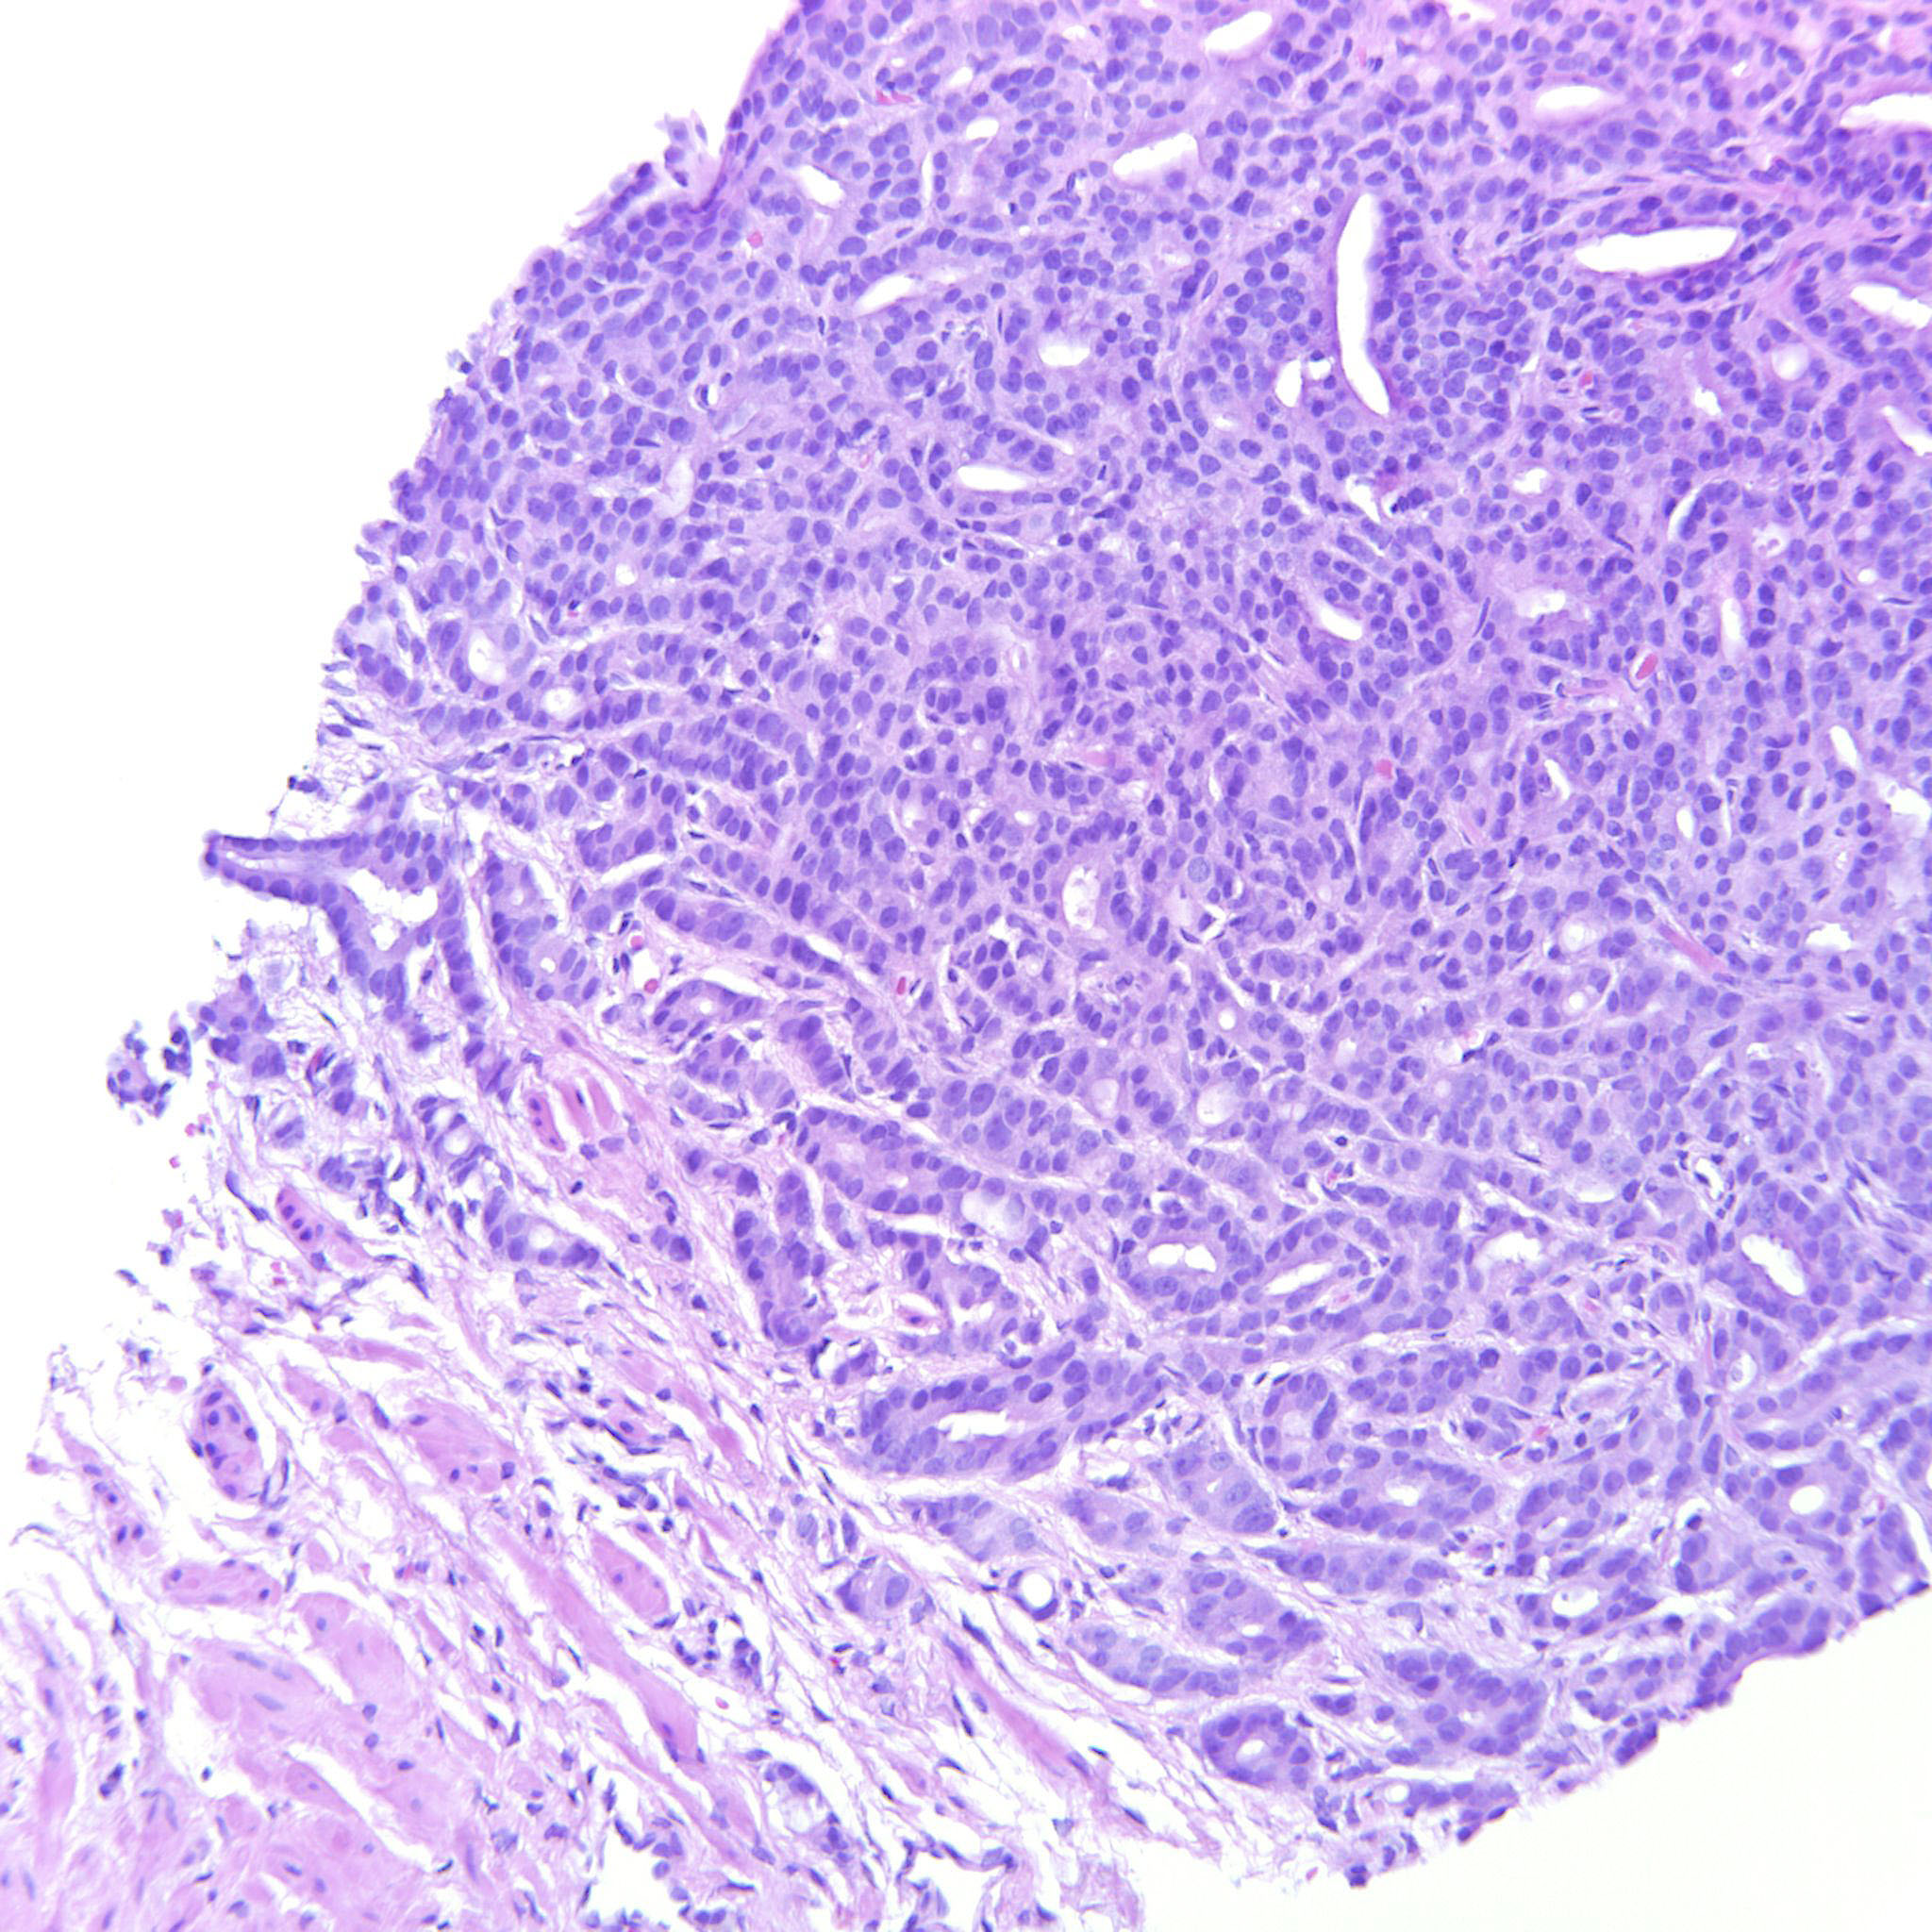

Prostate cancer grading

Case ID: 306